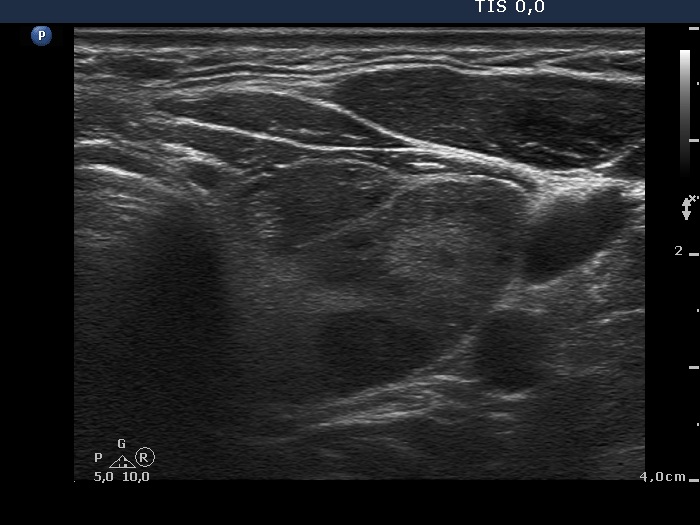

Oxyphilic adenoma (histological diagnosis) - case 1735 |

Papillary carcinoma (histological diagnosis) |

Both lesions have multiple cystic areas. The malignant case clearly belongs to spongiform cyst category because the cystic area exceeds 50% of the nodule. The risk of malignancy is very low in such lesions if there are no signs suggesting an increased risk. The solid part was hypoechogenic in these cases therefore aspiration cytology was mandatory. Note that both cases presented signs of posterior acoustic enhancement, i.e. hyperechogenic figures in the back wall of the microcystic areas. There was only one but an important difference between the cases. The benign nodule was located within the thyroid, while the malignant was found in a lateral aberrant thyroid tissue.